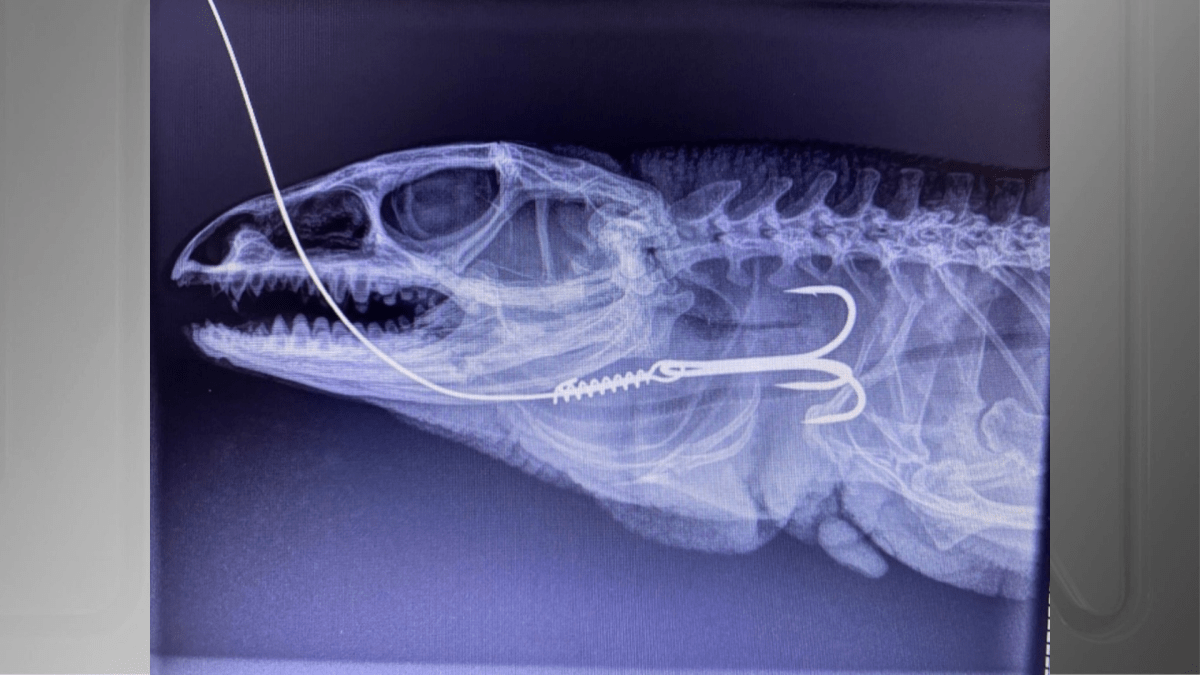

Segundo Júlio Souza, coordenador do Serviço de Atendimento de Animais Silvestres de Blumenau, o lagarto passou por uma cirurgia de esofagostomia para remoção da garateia.

Na sequência, o animal passou por uma cirurgia de reconstrução do esôfago. No pós-cirúrgico a equipe veterinária percebeu que o lagarto permanecia com uma ruptura próxima à entrada da cavidade celomática.

O animal foi resgatado pela Secretaria Municipal do Meio Ambiente e Sustentabilidade após ser encontrado com um anzol preso na boca.